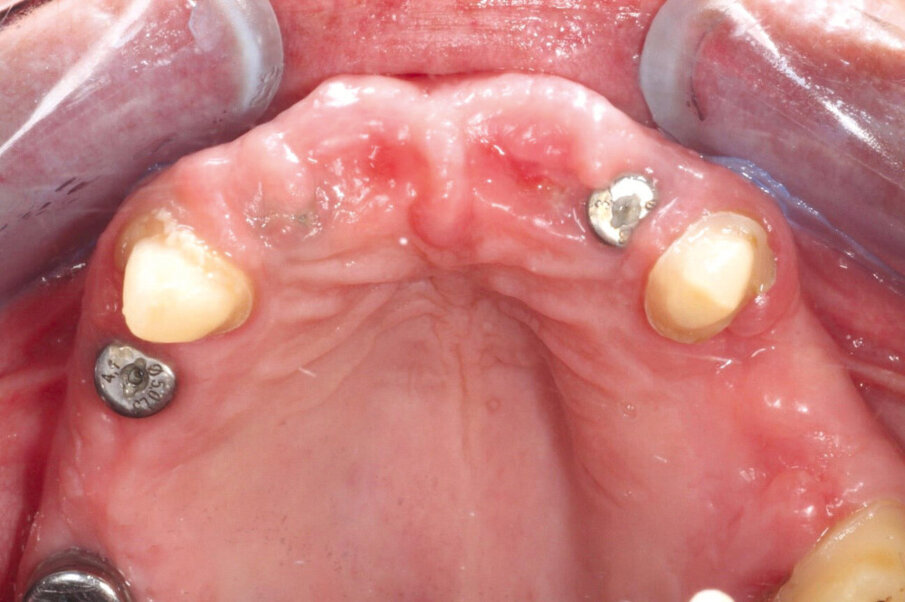

58-godišnjakinja, nepušačica i sistemski zdrav pacijent kojeg je njen doktor dentalne medicine uputio u naš centar radi implanto-protetske terapije. Pacijenticu je uglavnom smetala loša estetika u gornjem frontalnom području, koje je karakterizirala visoka linija osmijeha i izražene anomalije položaja zuba (Slike 1. i 2.), kao i funkcionalna ograničenja kao posljedica neugode prilikom žvakanja. Tri zuba su nedostajala u gornjoj distalnoj regiji i to zubi 17, 15 i 27 koji nisu bili protetski opskrbljeni, dok je u donjoj čeljusti u distalnoj regiji nedostajalo pet zuba s obje strane u području premolara te su oni zamijenjeni djelomičnom mobilnom protezom. Svi preostali zubi u gornjoj i donjoj čeljusti bili su prema klasifikaciji „Proceedings of the World Workshop on the Classification of Periodontal and Peri-implant Diseases and Conditions 2017“ imali parodontitis stadija IV, a prosječna dubina sondiranja parodonta je bila 5,6 mm. 7 Prosječni indeks krvarenja (BOP) i srednji indeks plaka (PI) bili su 70 odnosno 80 posto. S obzirom na paradontološke parametre i mjere oralne higijene (vidljivi kamenac i naslage), oralna higijena pacijentice klasificirana je kao loša. Pacijentica je u drugoj ordinaciji liječena s dva implantata u desnoj maksilarnoj stražnjoj regiji kako bi se zamijenili prvi pretkutnjak i prvi kutnjak (Slika 3). Prema definiciji koju je Weißgold uveo 1977. godine, pacijent ima debeli biotip. 26

Inicijalna terapija sastojala se od sustavnog parodontnog liječenja i redovitih kontrolnih pregleda s uputama i provjerama higijene zuba u razdoblju od tri mjeseca. Prva faza rehabilitacije maksile sastojala se od PET-a zajedno s postavljanjem implantata tipa 1.

U regijama dva lateralna maksilarna sjekutića 12 i 22 prema uputama iz „Proceedings of the Fourth ITI Consensus Conference (Chen et al., 2009)“ i očuvanjem grebena u lijevoj premolarnoj regiji (zubi 24 i 25) uporabom dentinskog grafta, dobivenog od dva izvađena lijeva maksilarna premolara. Zbog povećanog stupnja nestabilnosti zuba i jer se pomoću digitalne volumenske tomografije (CRANEX 3D Ceph, Soredex, KaVo Kerr) pokazalo da je bukalna kost vrlo tanka procijenjeno je da dva središnja maksilarna sjekutića 11 i 21 nisu prikladna za „Socket Shield“ tehniku (Slika 4). Umjesto toga, planiran je RST za oba sjekutića, kako bi se spriječila resorpcija bukalne koštane lamele i gubitak volumena alveolarnog grebena kao posljedica vađenja zuba.

Prva faza rehabilitacije gornje čeljusti uključivala je imedijatnu implantaciju u post-ekstrakcijske alveole dva bočna sjekutića, te je planirana SST napravljena samo na desnom bočnom sjekutiću.

Zbog povećane pokretljivosti zuba > 2, SST je bila kontraindicirana za lijevi bočni sjekutić i za oba premolara na lijevoj strani. Kliničke krunice dva središnja sjekutića su bile uklonjene, a korijene se pažljivo skraćivalo okruglim dijamantnim svrdlom uz hlađenje pomoću sterilne fiziološke otopine sve dok oba cervikalna ruba korijena nisu bila na udaljenosti od 3,0 mm do ruba gingive (Slika 5). U području desnog bočnog sjekutića, priprema SST je izvedena kako je opisano u publikaciji od Gluckmana i kolega. 12 Nakon vađenja su pretkutnjaci mehanički očišćeni, osušeni, a zatim s uređajem Smart Dentin Grinder (KometaBio) usitnjeni prema preporukama proizvođača. 4

Autologni dentinski graft korišten je na mjestima implantacije u regiji 22 i u obje ekstrakcijske alveole pretkutnjaka na lijevoj strani (Slika 6). Implantacija se napravila u ekstrakcijskim alveolama oba bočna sjekutića s dva implantata (BEGO Semados® RSX, BEGO Implant System) duljine 13 mm i promjera 3,75 mm (Slika 7.). Završno, područja između implantata i zida ekstrakcijske alveole popunjene su dentinskim graftom te je sve pokriveno PRF membranom s "Poncho" tehnikom.25 Nakon pripreme bukalnog i palatalnog tunela, postekstrakcijske alveole lijevih pretkutnjaka i u alveoli zadržanih korijena lijevog središnjeg sjekutića prekrivene su pomoću PRF membrana, prema Choukrounovoj metodi (A-PRF, mektron) napravljene centrifugiranjem s 1300 o/min u trajanju od 13 minuta. 10 Korijen desnog središnjeg sjekutića pokriven je s transplantatom vezivnog tkiva (connective tissue graft; CTG) koji je dobiven iz nepčane sluznice u desnom kvadrantu. PRF membrane i CTG postavljeni su u pripremljeni bukalni i nepčani tunel te su fiksirani resorbirajućim šavovima od monofilamenta 5.0 (Serafast 5.0, Serag Wiessner) (Slika 8.). Postoperativna rendgenska snimka pokazala je da su korijeni središnjih sjekutića dovoljno skraćeni, implantati ispravno pozicionirani u ekstrakcijskim alveolama bočnih sjekutića, te da su ekstrakcijske alveole pretkutnjaka pravilno napunjene dentiskim graftom (Slika 9.).